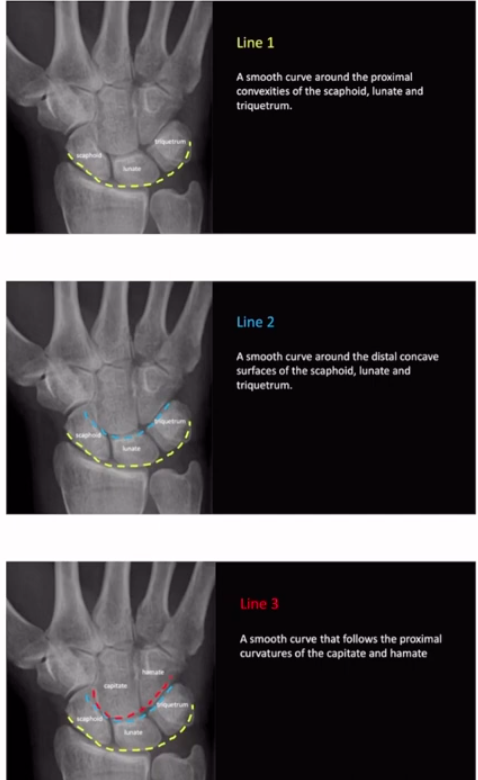

O que são os arcos de Giula?

arcos usados em incidencia posteroanterior para avaliar alinhamento entre as fileiras carpais (essa relação se perde com incidencia anteroposterior)